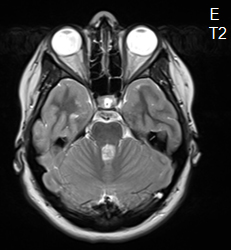

La rosette à deux compartiments

Dr Arnault Tauziède-Espariat AP-HP Lariboisière - Paris

Données cliniques :

Patiente âgée de 17 ans, sans antécédents particuliers, hospitalisée pour des céphalées et des vertiges d’apparition progressive en trois semaines. Tableau clinique rapidement aggravé d'un syndrome d’hypertension intracrânienne et d'une diplopie binoculaire.

IRM cérébrale :

Processus expansif de la ligne médiane sous la forme d’une masse solide bien limitée, mesurant 3,2 cm de diamètre, centrée sur le quatrième ventricule avec extension vers l’aqueduc de Sylvius et le tronc cérébral.

Lésion en hyposignal T1 et hypersignal T2, rehaussée par le gadolinium de façon focale.

Hydrocéphalie obstructive et œdème modéré associés.

Pas de remaniements hémorragiques ou de calcifications.

Quel est votre diagnostic ?